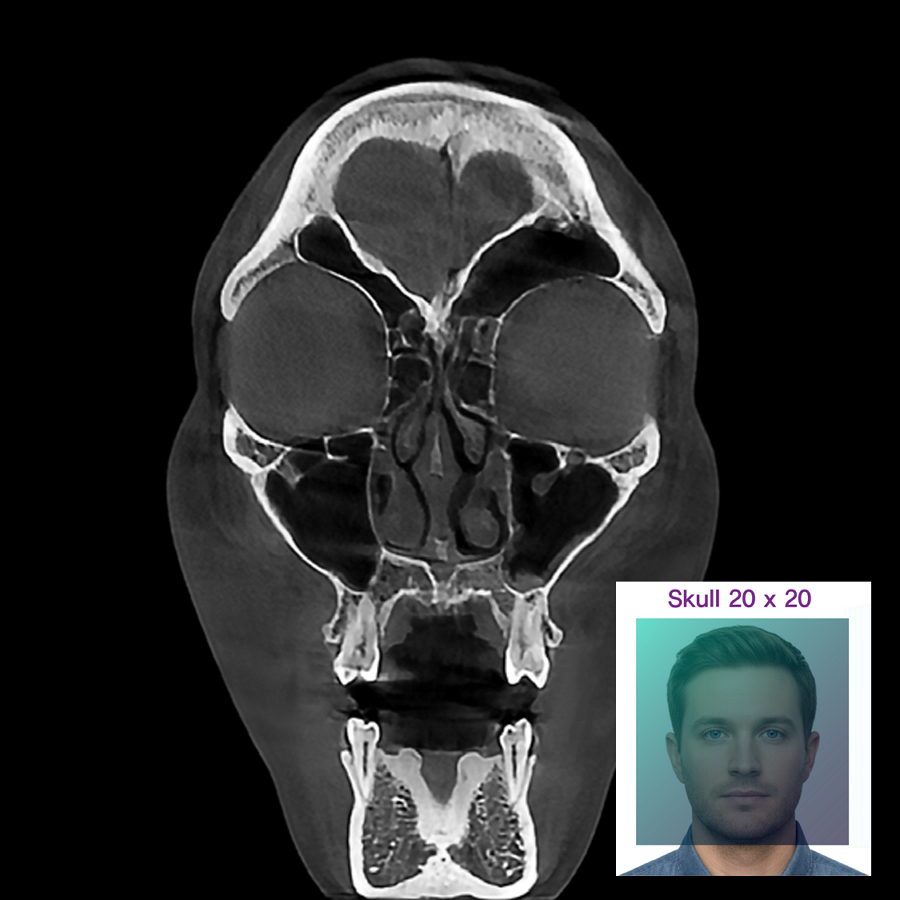

자유롭게 설정 가능한 FOV와 최대 20x20cm의 대면적 촬영기능은 국소부위의 진단부터 두개골 천체의 분석까지 폭넓게 사용될 수 있습니다.

0.20mm Voxel의 고해상도 촬영은 진단에 중요한 구조들을 선명히 확인할 수 있게 해줍니다. 이 제품은 국내 CBCT 진단참고수준(DRL)보다 약 79% 낮은 방사선 노출로 보다 안전하고 안심할 수 있는 진료환경을 제공합니다.

분석 정확성과 치료계획 지원을 위해 2D 이미지를 3D 이미지로 변환하여 환자의 얼굴 윤곽과 해부학적 구조의 직관적인 확인을 돕습니다.